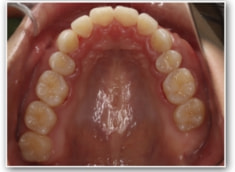

治療後